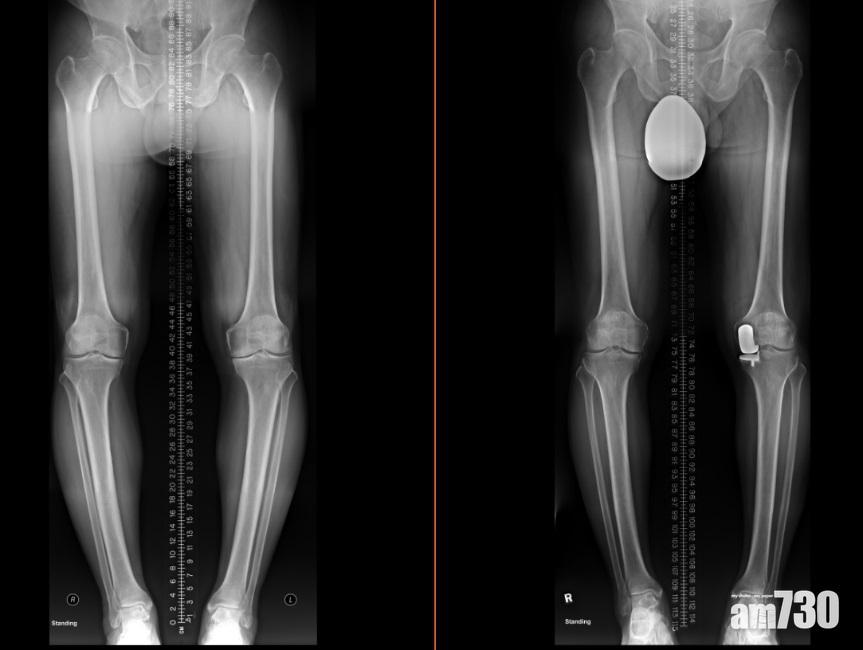

當膝關節的軟骨嚴重磨蝕,甚至出現骨磨骨情況,屆時患者就要接受關節置換手術。李醫生指出,過去較常用的「全膝關節置換手術」,成效顯著,但它的缺點是,即使患者不是整個關節出現退化,也得把全個關節換走,一併把正常組織完全移除,對患者而言並非最大效益,故衍生出「半膝關節置換手術」,只換走需要移除的部份,保留健全的組織。

半膝關節置換(右)保留了健康的組織,患者康復後走路的姿勢更自然。(圖片由醫生提供)